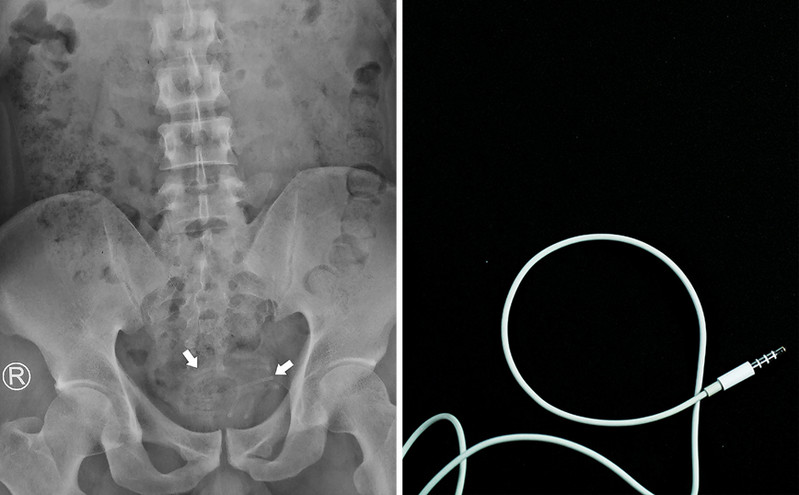

Πήγε με στομαχόπονο στο νοσοκομείο και βρέθηκε με καλώδιο ακουστικών στην ουρήθρα του